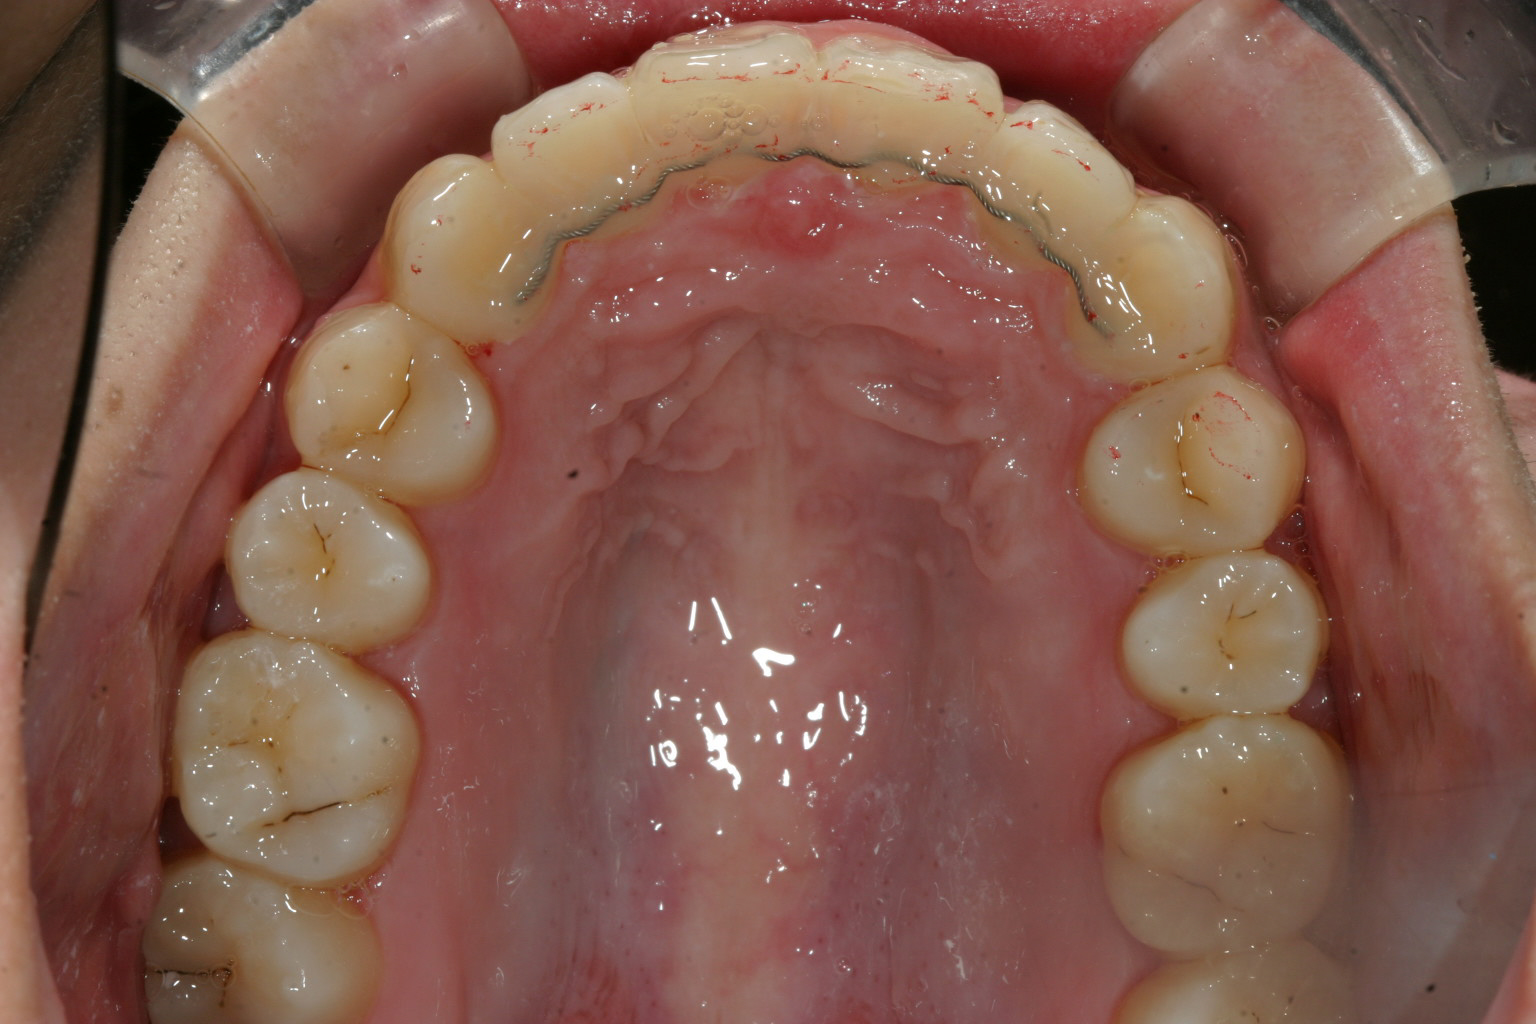

歯列がV字になっている為犬歯と犬歯の幅が狭く前歯が前に飛び出してます。

抜歯もせず綺麗なU字形に治りました。